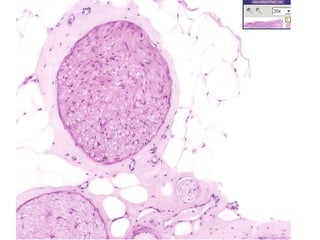

NEUROPATHY, Neoplastic

Benign: Schwannoma

Malignant: Malignant Schwannoma

Antoni A: “Palisaded”

Antoni B: NON-Palisaded

• #47 Schwannoma But really, could this be ANY soft tissue tumor?

• #48 Antoni A: Palisading, “Verocay” bodies Antoni B: Edema, “myxoid”